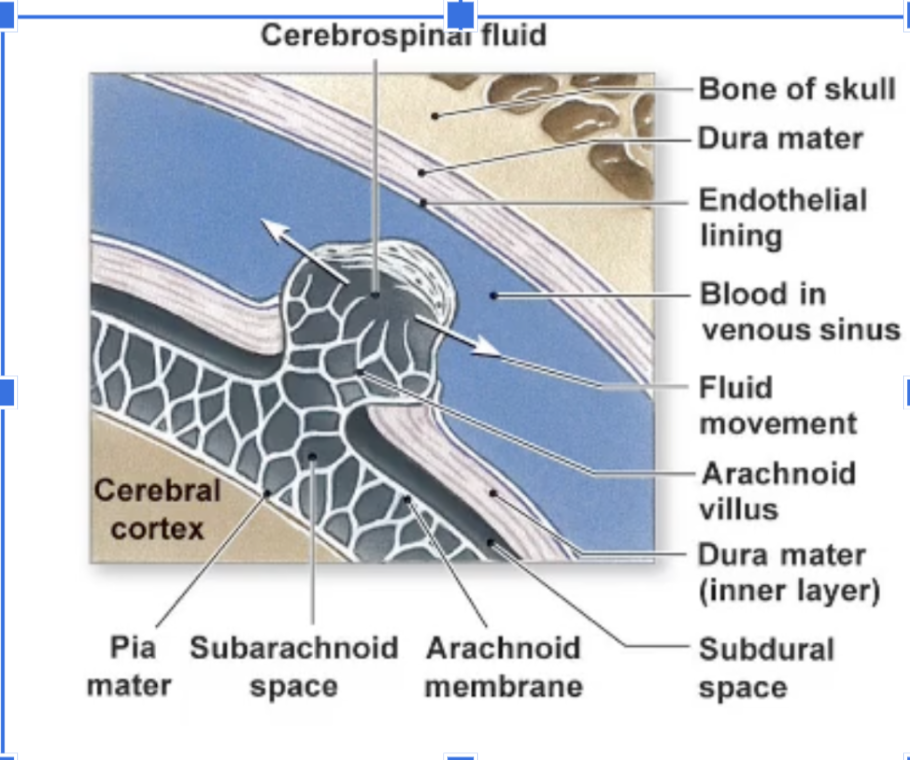

What are the three layers of the Cranial Meninges (thickest to thinnest)?

Dura Mater,Arachnoid Mater, Pia Mater

Which meningeal layer is thick, fibrous, provides physical protection, and is where brain bleeds occur when damaged?

The Dura Mater.

Which meningeal layer is thin, fibrous, looks like a web, and contains the cerebrospinal fluid (CSF)?

The Arachnoid mater

Where is the CSF located relative to the Arachnoid mater?

In the Subarachnoid space

Which meningeal layer is very thin, the deepest layer, and follows all the grooves of the brain?

The Pia mater.

How is excess CSF drained?

flows into the arachnoid villi where it is drained into dural venousus sinus with the blood